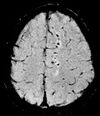

Effective T2 or "T2-star" |

T2* |

Postexcitation refocused GRE with small flip angle.[71] |

Low signal from hemosiderin deposits (pictured) and hemorrhages.[71] |

| Susceptibility-weighted |

SWI |

Sensitive for blood and calcium, by a fully flow compensated, long echo, gradient recalled echo (GRE) pulse sequence to exploit magnetic susceptibility differences between tissues

|

Detecting small amounts of hemorrhage (diffuse axonal injury pictured) or calcium.[91]